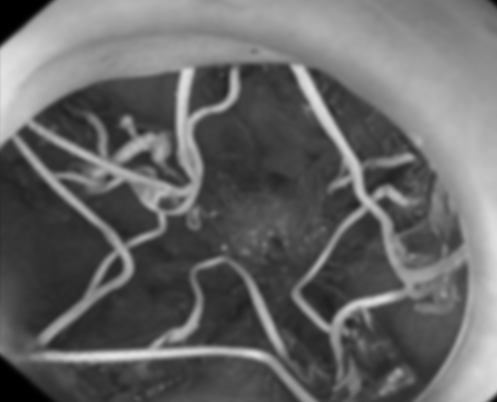

广东省第二人民医院消化医学部主任、主任医师梁彪向吴小姐介绍了胃转流支架技术:“我们通过胃镜在十二指肠球部放置胃转流支架,形成临时性‘食物旁路’——让食糜在套管内‘与世隔绝’,胆汁胰液等消化液成功被隔离在套管外,二者在空肠这个主要吸收区域始终保持‘河水不犯井水’的状态,无法接触融合开启化学性消化,从而减少有效消化‘肠’道,让糖与脂肪的吸收大打折扣,达到减重目的,同时避免永久性器官改变。”

手术过程中,梁彪主任在内镜的精准引导下,通过特制的输送系统将胃转流支架置入十二指肠球部。支架顺利展开后,成功形成新的食物通道。手术仅耗时半小时,体现了微创手术的高效优势。